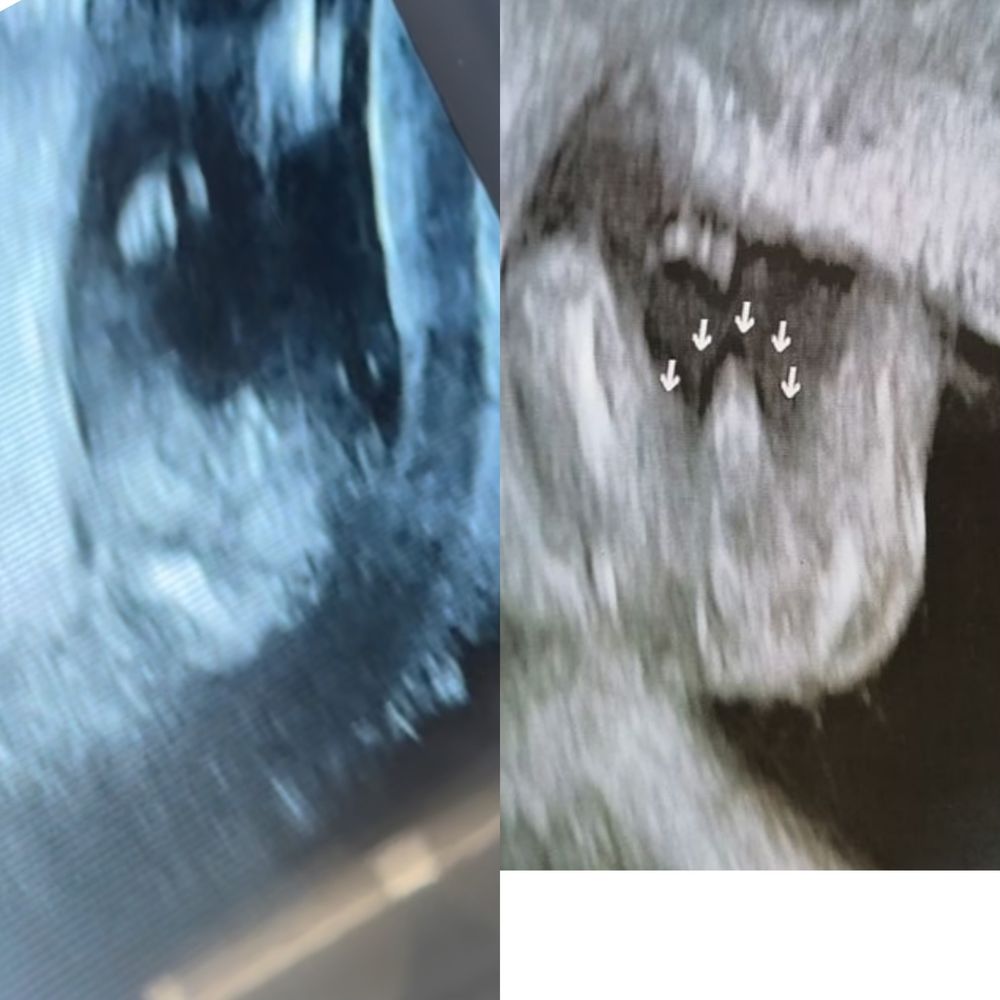

Яна, вот нашла в интернете фото узи мальчик 16 нед. Мне показалось похожим на наше. Справа интернет слева мы. Изображение

10.10.2023

Karmilla, во) сын 16 недель Изображение

Karmilla, а мне кажется похож на мое фото))) отпишу послезавтра после скрининга